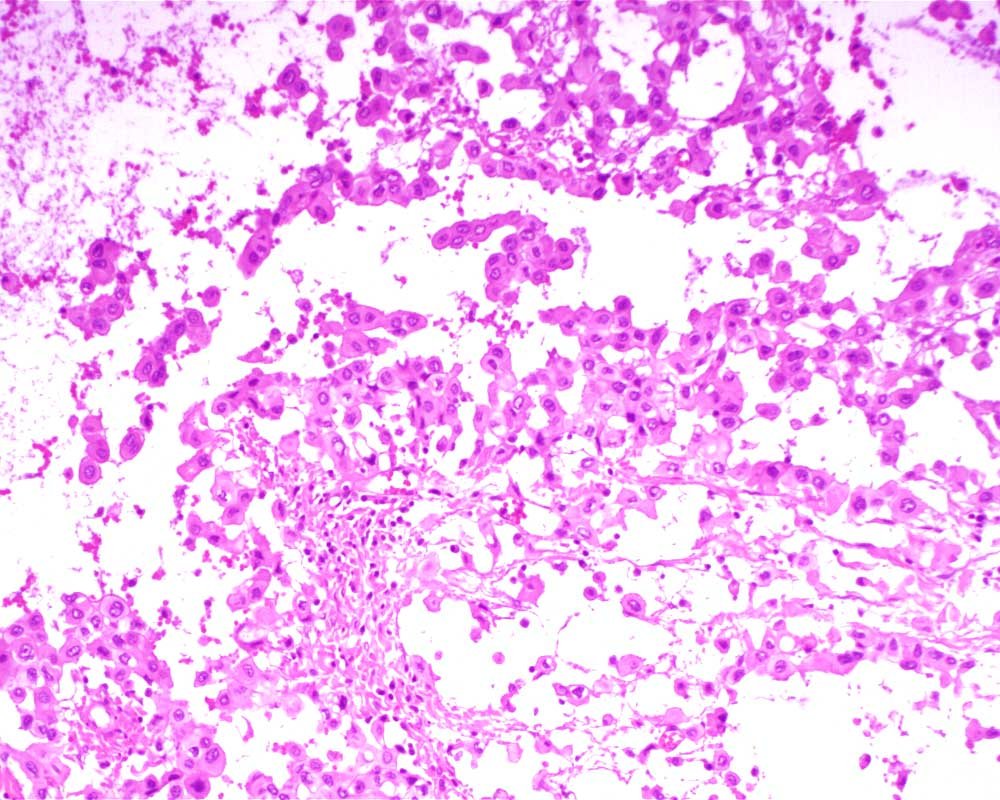

Case: PeritonealLesion

Final Diagnosis: